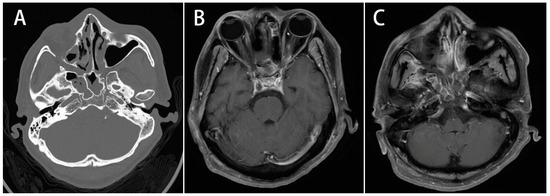

Figure 3.

Image study of case 3. A 44-year-old man with a history of poorly controlled diabetes presented with eyelid swelling, blindness, alert mental status, mydriasis, fever, and headache. (A): Axial contrast-enhanced CT scan. CT scan revealed rhinosinusitis over bilateral sphenoid sinuses, complicated with subperiosteal empyema, bony wall erosion, and right orbital infection. (B,C): Axial T1-weighted MRI images. MRI showed bilateral bulging of the cavernous sinus and signal enhancement over cavernous sinus and skull base under T1-weighted images.